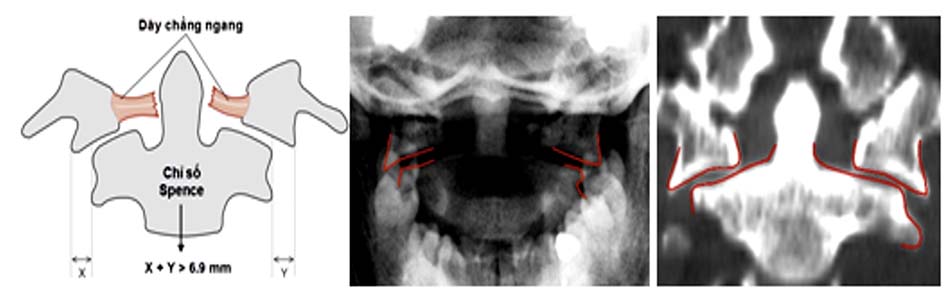

Từ khi có chụp cắt lớp và cộng hưởng từ, người ta có thể phát hiện các thương tổn dây chằng ngang phối hợp với vỡ C1, vì vậy hầu hết đều thống nhất chia làm 2 loại:

- Vỡ C1 đơn thuần: thương tổn vững, điều trị bảo tồn.

- Vỡ C1 kèm rách dây chằng ngang: vỡ cung sau và cung trước C1 có thể làm căng rộng sang bên của hai khối bên gây rách dây chằng ngang. Spence và cộng sự [41] nghiên cứu trên tử thi thấy khi khối bên căng rộng quá 6,9 mm sẽ gây rách hoàn toàn dây chằng ngang. Đây là thương tổn mất vững và dễ di lệch thứ phát [48].

Khi chỉ số Spence > 6,9 chẩn đoán xác định đứt dây chằng ngang, tổn thương mất vững [11] [30] [42].